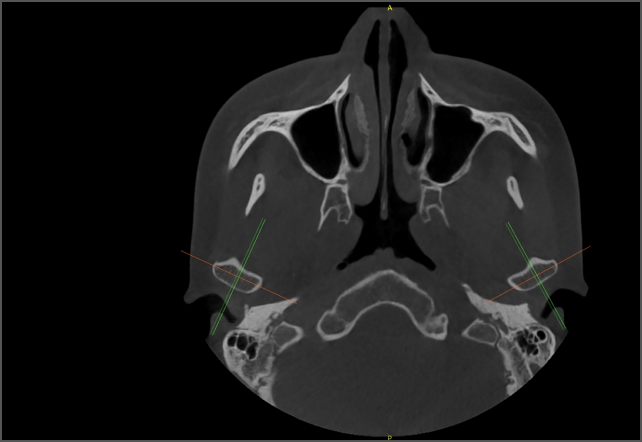

• lamtau AI牙弓曲線

AI牙弓曲線

• lamtau AI TMJ

AI TMJ